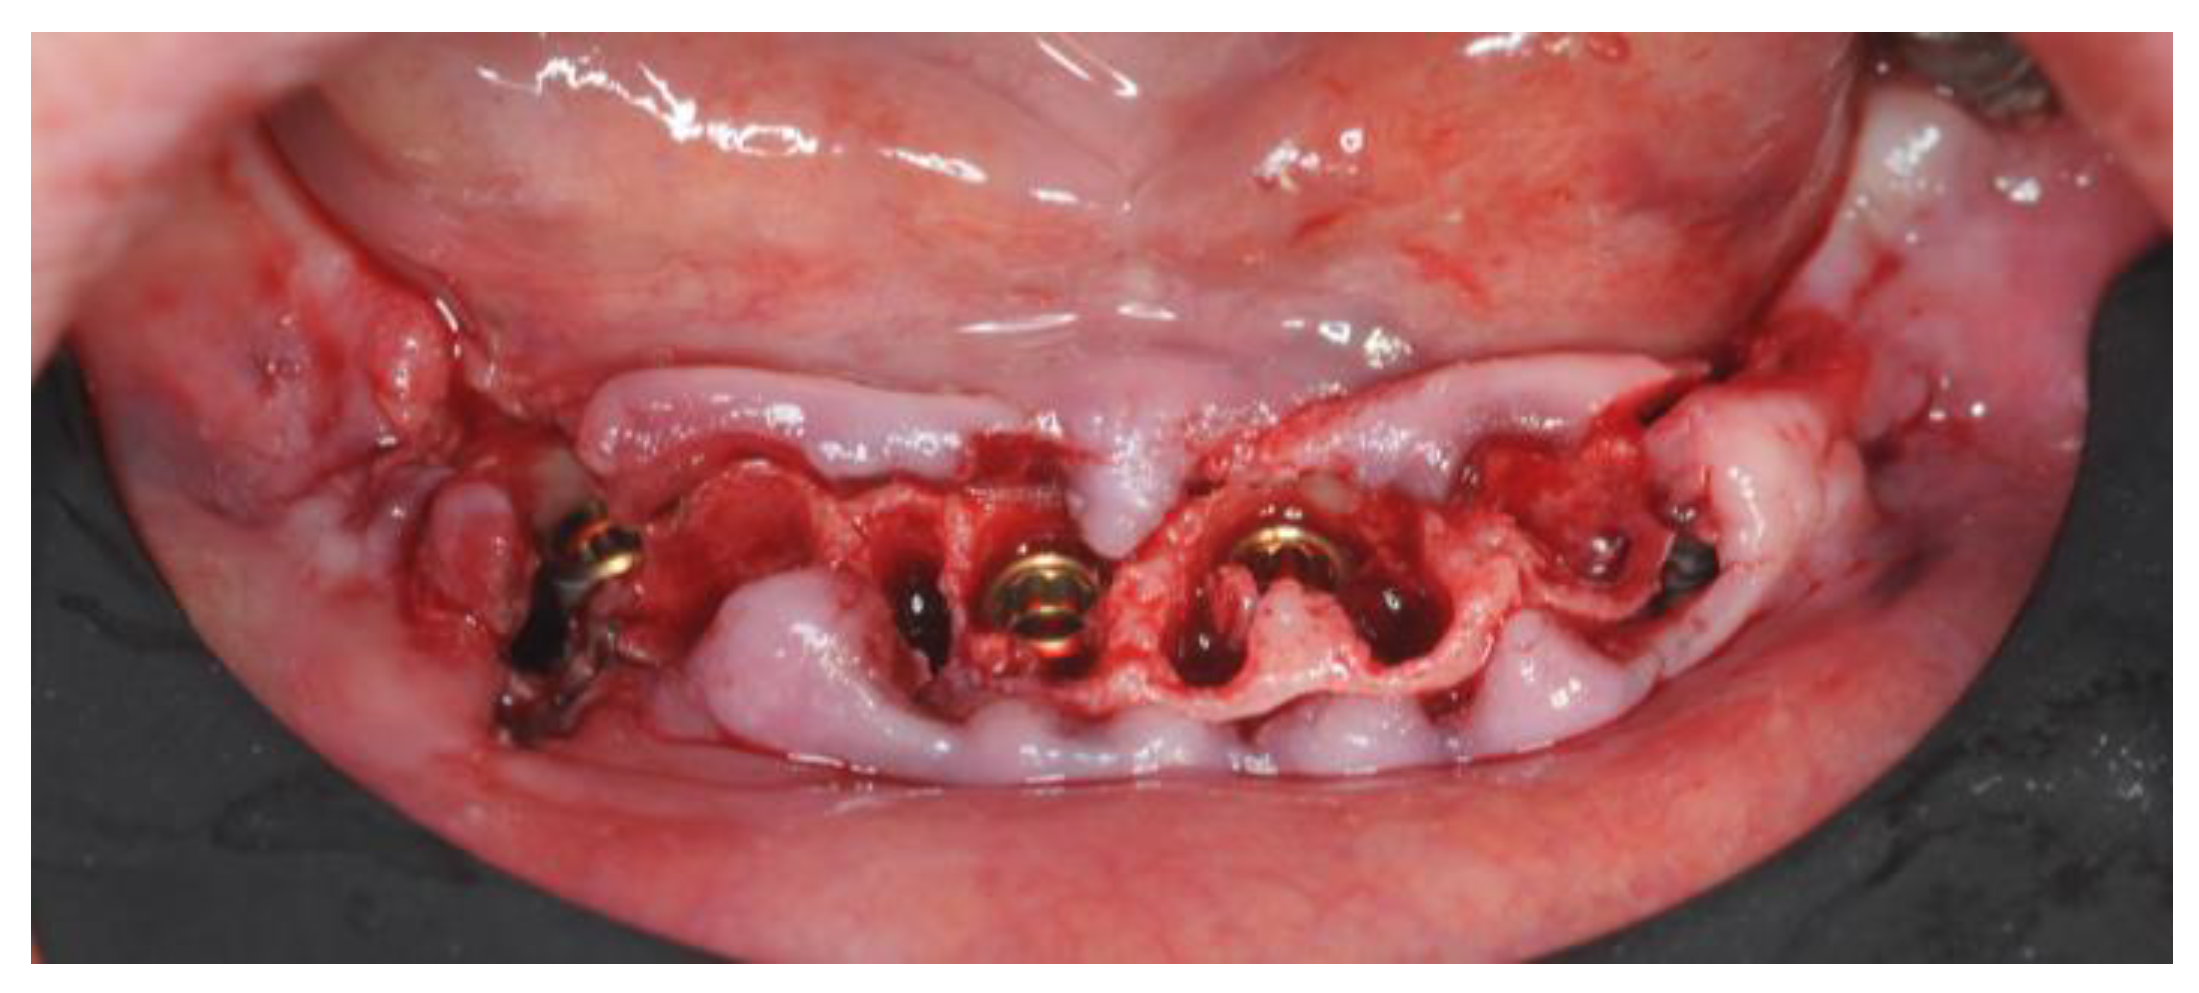

2.4. Surgery